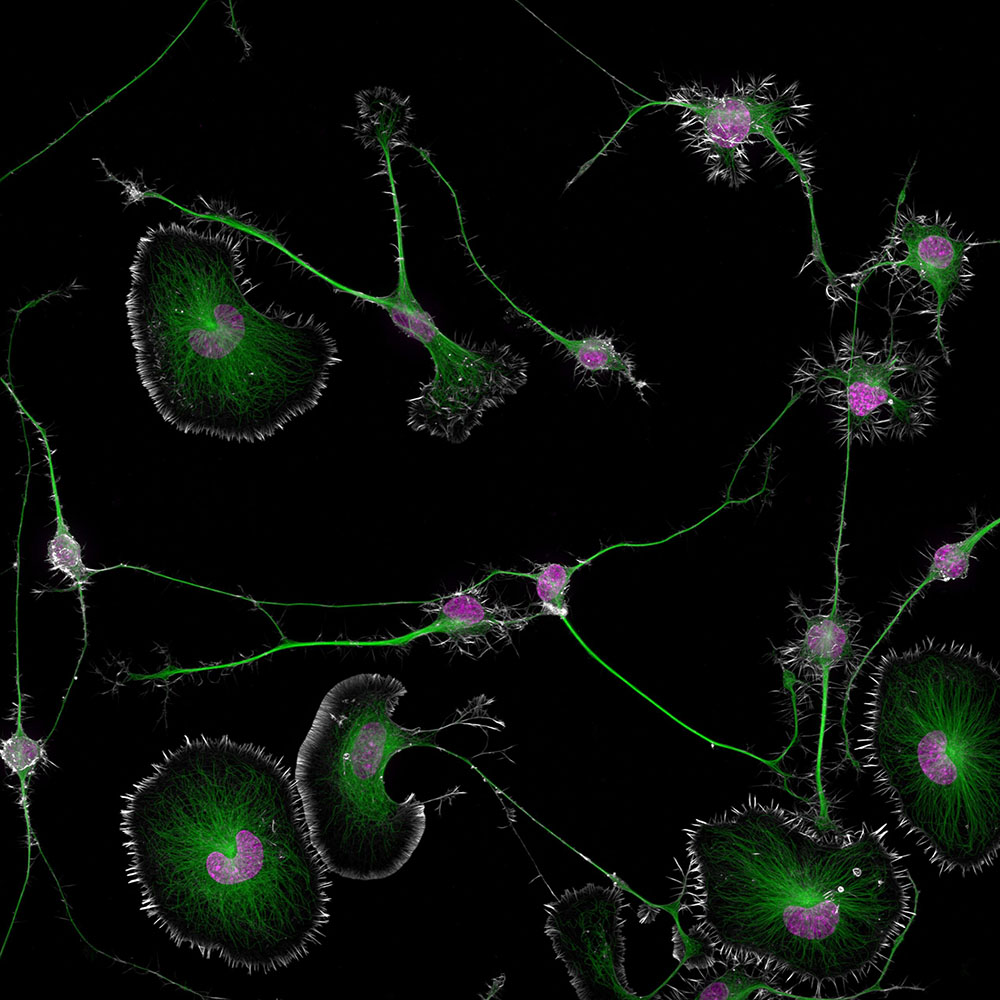

Ο 50ός διαγωνισμός φωτογραφίας Nikon Small World Photomicrography είχε πολλές χιλιάδες συμμετοχές από επιστήμονες και καλλιτέχνες παγκοσμίως και εντυπωσίασε ιδιαίτερα, με την πρώτη θέση να παίρνει μια μοναδική αποτύπωση κυτταρικών όγκων εγκεφάλου! Ο νικητής του πρώτου βραβείου είναι ο Dr. Bruno Cisterna ο οποίος με τη βοήθεια του Dr. Eric Vitriol απαθανάτισε κύτταρα καρκινικού όγκου από τον εγκέφαλο ενός ποντικιού. Και οι 2 είναι ερευνητές στο Τμήμα Νευροεπιστημών και Αναγεννητικής Ιατρικής στο Πανεπιστήμιο Augusta των ΗΠΑ. Στην εικόνα φαίνονται εκπληκτικές λεπτομέρειες όπως ο σκελετός του κυττάρου, οι σωλήνες αλλά και οι πυρήνες της δομής, αποκαλύπτοντας τις διαταραχές που προκαλεί ο καρκίνος σε κυτταρικό επίπεδο.

Σύμφωνα με έρευνα του Dr. Cisterna αποκάλυψε ότι μια πρωτεΐνη ζωτικής σημασίας για τη δομή του κυττάρου με ονομασία profilin 1 (PFN1), παίζει βασικό ρόλο στη διατήρηση των οδών που είναι απαραίτητες για τη μεταφορά στοιχείων μεταξύ των κυττάρων. Όταν η πρωτεΐνη PFN1 διαταράσσεται, αυτοί οι σωλήνες δυσλειτουργούν, κάτι που οδηγεί σε κυτταρική βλάβη παρόμοια με αυτή που παρατηρείται σε νευροεκφυλιστικές ασθένειες (όπως ALS και Alzheimer). Ο Dr. Cisterna πρόσθεσε το εξής:

Πέρασα περίπου 3 μήνες τελειοποιώντας τη διαδικασία που χρειάζεται για να εξασφαλίσω καθαρή ορατότητα των κυττάρων. Όταν το πέτυχα, αφού άφησα 5 ημέρες για να διαφοροποιηθούν τα κύτταρα έπρεπε να βρω το σωστό οπτικό πεδίο όπου αλληλεπιδρούν τα διαφοροποιημένα και τα μη διαφοροποιημένα κύτταρα. Αυτό χρειάστηκε περίπου 3 ώρες παρατήρησης κάτω από το μικροσκόπιο για να συλλάβω την κατάλληλη στιγμή.